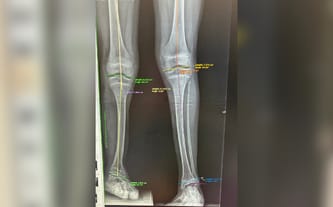

Wiedzieliśmy, że Miki urodzi się bez kości strzałkowej. On rozwijał się pod moim sercem a ja szukałam podobnych do niego przypadków, a później kontaktu do najlepszych specjalistów. Gdy powitaliśmy Mikusia na świecie obiecaliśmy mu, że zrobimy wszystko, by w przyszłości był sprawnym człowiekiem. Ta misja towarzyszy nam każdego dnia.

Dzięki pomocy wielu wspaniałych ludzi to się udało. Nasz synek przeszedł z powodzeniem bardzo skomplikowaną operację zdeformowanej nóżki, miał założony aparat Ilizarowa do wydłużania kończyny, a następnie przeszedł intensywną rehabilitację.

Dzięki wsparciu poprzedniej zbiórki jesteśmy już po pierwszym zabiegu wydłużania! Udało się wydłużyć nogę o 6 centymetrów! Po rehabilitacji Miki mógł już oficjalnie odrzucić kule i powoli wracać do formy.

Ale to jeszcze nie koniec walki. Czeka nas kolejna operacja wyciągnięcia płytki w kolanie. To kolejne koszty, ale jesteśmy ogromnie szczęśliwi, że zabieg się udał. Teraz musimy doprowadzić sprawę do końca. Bez Was nie bylibyśmy w tym miejscu.